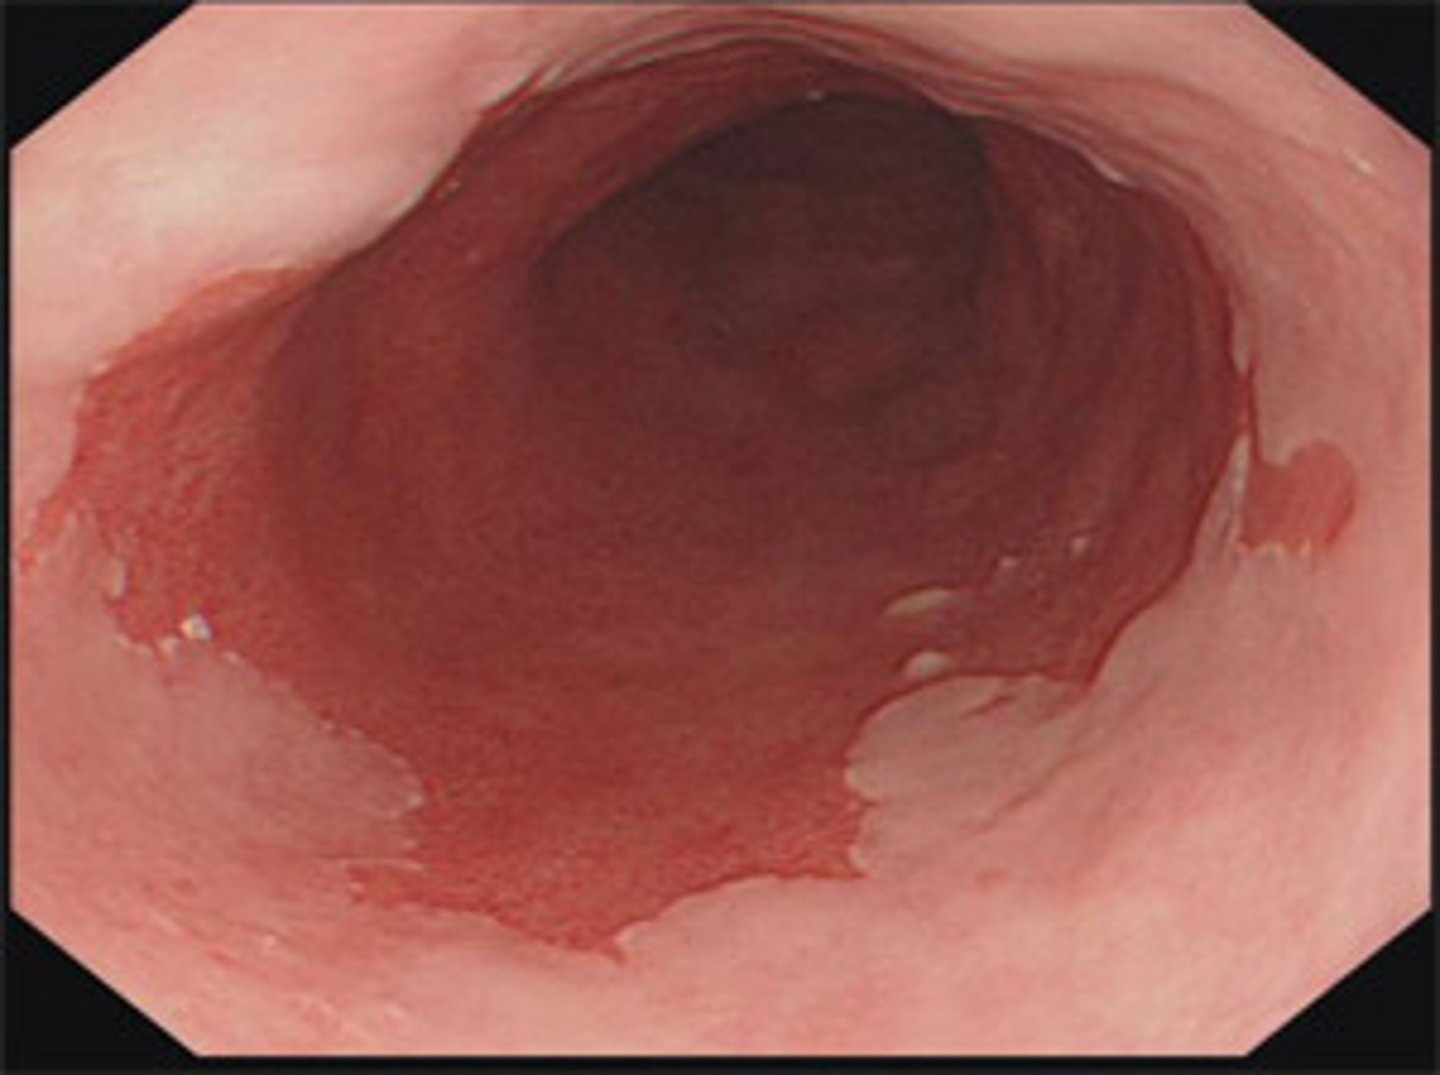

Jim is a 70 year old white man with GERD. He has had GERD for the past 6 years. You decide to screen him for Barrett's esophagus since he has two or more risk factors.

What test do you run?

What do you need to order to confirm the diagnosis?

What do you treat him with?

1.) Endoscopy

2.) Biopsy is needed for diagnosis

3.) Long-term PPIs once or twice daily to control reflux symptoms

In a patient with barrett's esophagus, how often should you perform an endoscopy if no dysplasia is present?

Every 3-5 years

Amy is a 51 year old woman with barrett's esophagus. She has high grade dysplasia and adenocarcinoma. What therapy should she undergo?

Endoscopic therapy

She needs to have an endoscopy every 3-6 months.

Richard a 65 year old man with Barrett's esophagus has low grade dysplasia. How often should he receive endoscopic therapy?

Every 6-12 months

Barrett's esophagus

What is this image of? It is salmon colored.